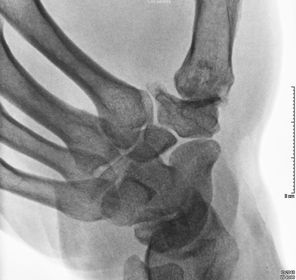

Condílea: Es biaxial, movimientos en 2 planos (Sagital y coronal). forma elipsoidea. Ejemplo: Radiocarpiana.